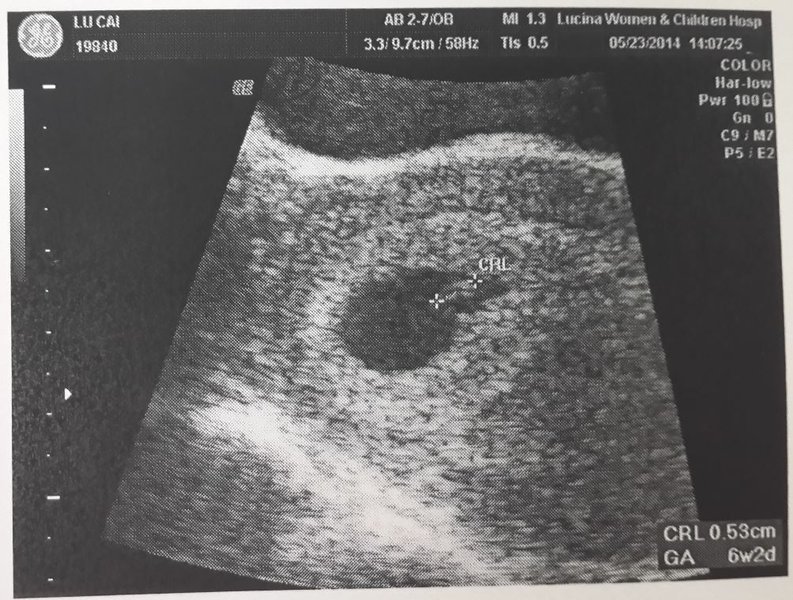

你好~這是我的給你當參考

CRL是胚胎頭到臀的長度~胚囊是整個黑黑的圓形~

有些發育小一點或晚一點馬咪不要太操心唷~有聽說8~10周才照到心跳的例子